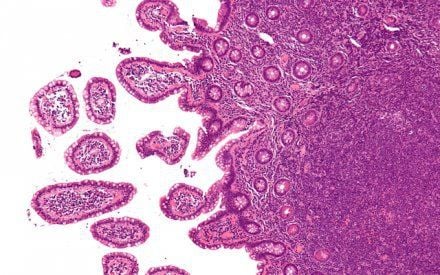

Hình ảnh tế bào viêm tuyến giáp dạng hạt (bán cấp)